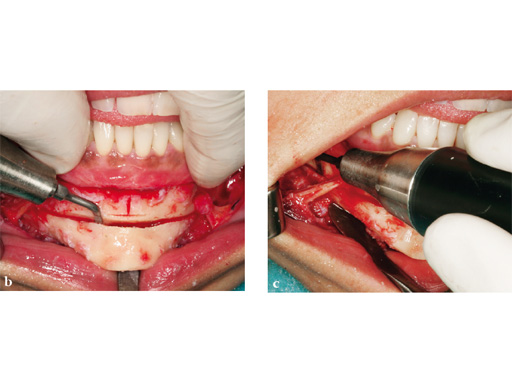

Case 1: A patient after multiple failed chin implants. Here piezosurgery proved to be superior to other oscillating instruments due to the controlled brush-type cutting motion, closeness to vulnerable structures which could be easily preserved, like the mental nerve on both sides, and protection of floor of the mouth vessels after completing the lingual corticotomy.

Case provided by Nils-Claudius Gellrich, Hannover, Germany